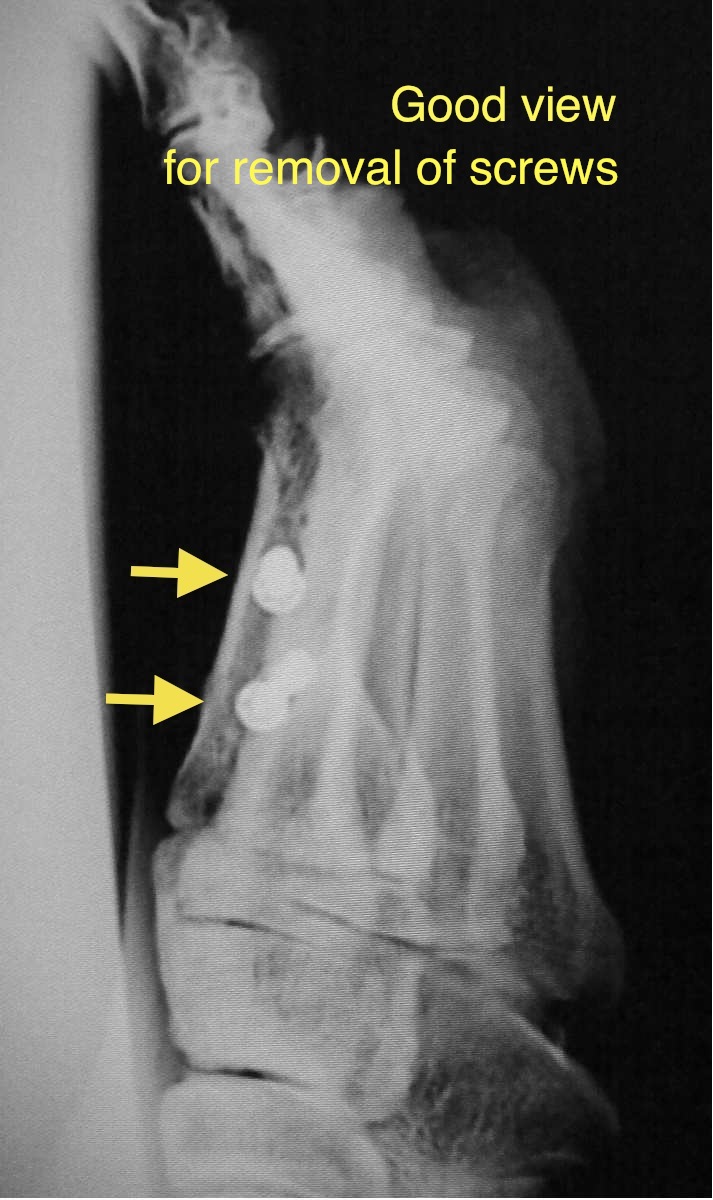

xp_removal_good_view.jpg 術後4ヵ月で足関節ブロック、透視下でスクリュー抜去を行う。透視下にスクリューを真上から見て、皮切の前に1.6mmガイド・ピンを手でスクリューに刺す。皮膚にスクリューの頭が通るようにガイド・ピンの周囲に5mmの皮切を加える。ガイド・ピンに中空ドライバーを刺して抜去する。

xp_removal_bad_view.jpg スクリュー抜去の時に透視下でスクリューを横から見て行うと難しくなる。